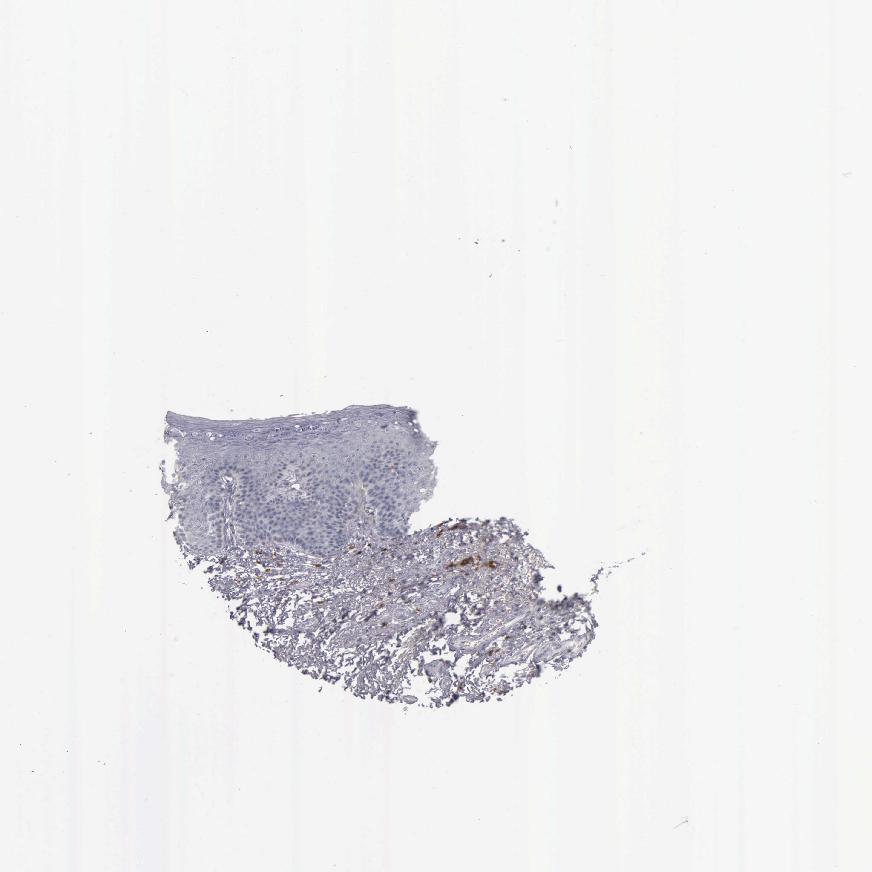

SKIN 2 - Antibody stainingi

Antibody staining in the annotated cell types in the current human tissue is reported as not detected, low, medium, or high, based on conventional immunohistochemistry profiling in selected tissues. This score is based on the combination of the staining intensity and fraction of stained cells.

Each image is clickable and will lead to virtual microscopy that enables deeper exploration of all samples and also displays staining intensity scores, fraction scores and subcellular localization as well as patient and tissue information for each sample.

Antibody HPA040957Antibody HPA043955Antibody CAB000010Antibody CAB072863Antibody CAB072864

Epidermal cells Not detectedNot detectedNot detectedNot detectedNot detected